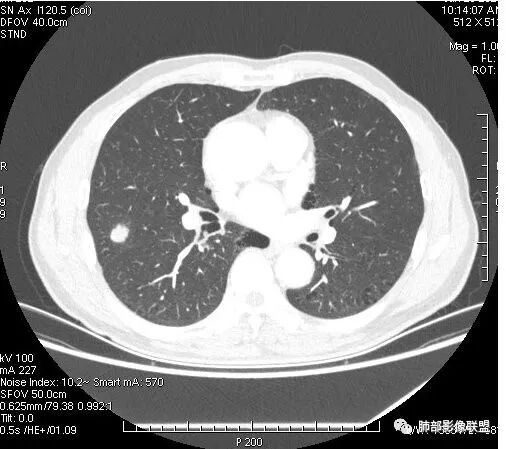

患者右上肺占位,内部强化不均,有空泡,有血管穿过,血管聚集现象,似有胸膜牵拉,考虑恶性

右肺上叶后段占位病灶,病灶不规则,周围胸膜线性牵拉,病灶部分周围有晕,病灶内见不规则空洞,未见明显引流支气管,长毛刺,多分叶、肿块边缘部分L型,可见血管直接供养。增强见点状坏死、病灶内血管。综上考虑恶性可能性大,鉴别隐球菌。

右肺上叶结节,浅分叶膨隆,边缘可见胸膜牵拉及血管集束,不规则厚壁空洞,不均匀强化,血管进入病灶,边缘毛燥,考虑低分化腺癌,鉴别隐球菌。

有空泡征,实性部分密度均匀?强化均匀?

内部血管怎么样?

支气管?

有血管穿行

部分地方膨隆,血管进入增粗

右肺上叶结节,周围毛刺明显,其内有小炮征,分叶,强化中度,其内可见坏死,支气管有截断,考虑腺癌,鳞癌待排。病灶的上缘有一个小支气管进入,然后截断了